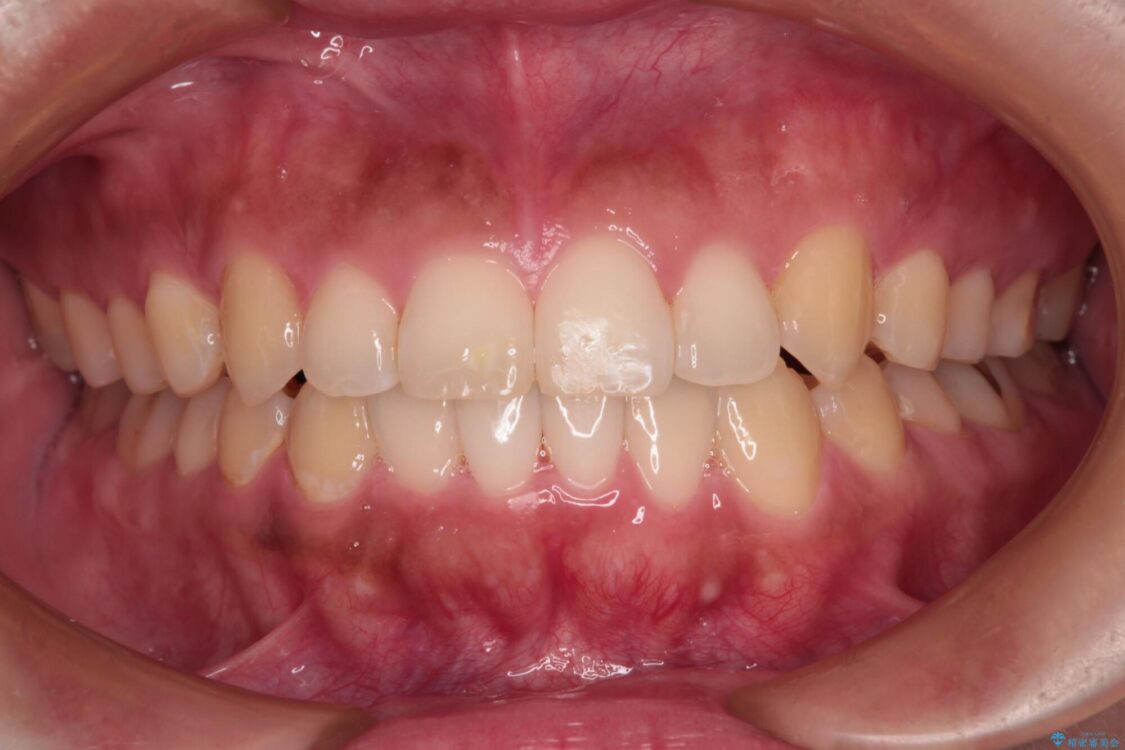

治療後

• 【モニター】カリエール・ディスタライザーを併用した八重歯のインビザライン矯正 治療後画像